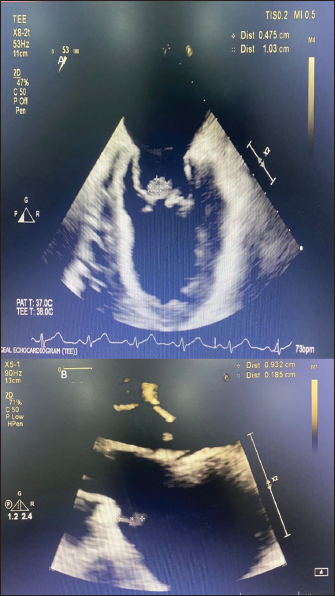

Computed tomography of the thorax revealed prominent mediastinal nodes, the largest measuring 1.2 cm on the short axis. Trans-thoracic echocardiography was done which showed probable vegetation measuring 19 × 3 mm on the anterior mitral leaflet (AML) and posterior mitral leaflet, and severe mitral regurgitation. A trans-esophageal echocardiography was done and confirmed the findings (Fig. 1A). Bronchoscopy and endobronchial ultrasound-guided fine needle aspiration of the enlarged mediastinal lymph node were done and were unrevealing. Two sets of blood cultures which were sent 4 days apart both grew P. aeruginosa sensitive to piperacillin-tazobactam [Minimum inhibitory concentration (MIC) – 8 µg/ml], amikacin (MIC - 4 µg/ml), ceftazidime (MIC - 2 µg/ml) and cefepime (MIC - 2 µg/ml). A previous blood culture which was sent from a local hospital prior to admission at our centre was also traced and had grown P. aeruginosa with a similar susceptibility pattern. IV piperacillin-tazobactam in a renally adjusted dose was continued and vancomycin was stopped based on susceptibility testing results. The need for valve replacement due to the difficulty in eradicating the infection with medical therapy alone was explained to the patient’s relatives, however, he was unfit for surgery at that point of time.

Echocardiography repeated after a week at a follow-up visit showed decreased size of the vegetation on AML to 3 × 8 mm (Fig. 1B). There was no worsening of hearing as assessed by PTA repeated after a week of starting amikacin (Fig. 2B). An echocardiography repeated after 3 weeks showed complete resolution of the vegetation on AML and decrease in the size of vegetation on PML to a tiny strand-like structure. Meanwhile he also complained of hearing loss. PTA was repeated and showed moderately severe bilateral sensory neural hearing loss - 68 db in the right ear and 56 db in the left ear (Fig. 2). Hence the antibiotic regimen was stopped and a short course of prednisolone 1 mg/kg tapered over 2 weeks was given without much symptomatic benefit. He was later planned for cochlear implantation as a hearing aid.

Fig. 1. (A): Transesophageal echocardiography showing vegetation on anterior and posterior mitral leaflets prior to starting combination therapy. (B): Trans-thoracic echocardiography done after a week of combination antibiotic therapy showing decrease in size of vegetation on AML.